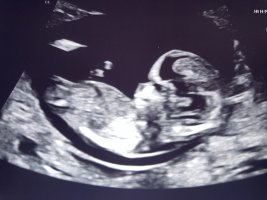

Ser ut som en jenteHåper det er nub på noen av disse (aner ikke hva man ser etter)

14+2 i dag, og navlestrengen lå mellom beina. Nurket sov og gjespet, ville ikke flytte på seg

Vis vedlegget 427759Vis vedlegget 427760Vis vedlegget 427761